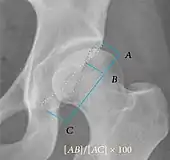

Measurements of impingement on X-ray.[notes 1][20]

Femoral head-neck offset

Measured in cross-lateral view.

Offset of the femoral head with regard to most prominent aspect of the femora neck>10 mm

Offset percentage Femoral head-neck offset related to femoral head diameter >0.18

• less indicates high risk of cam type impingement